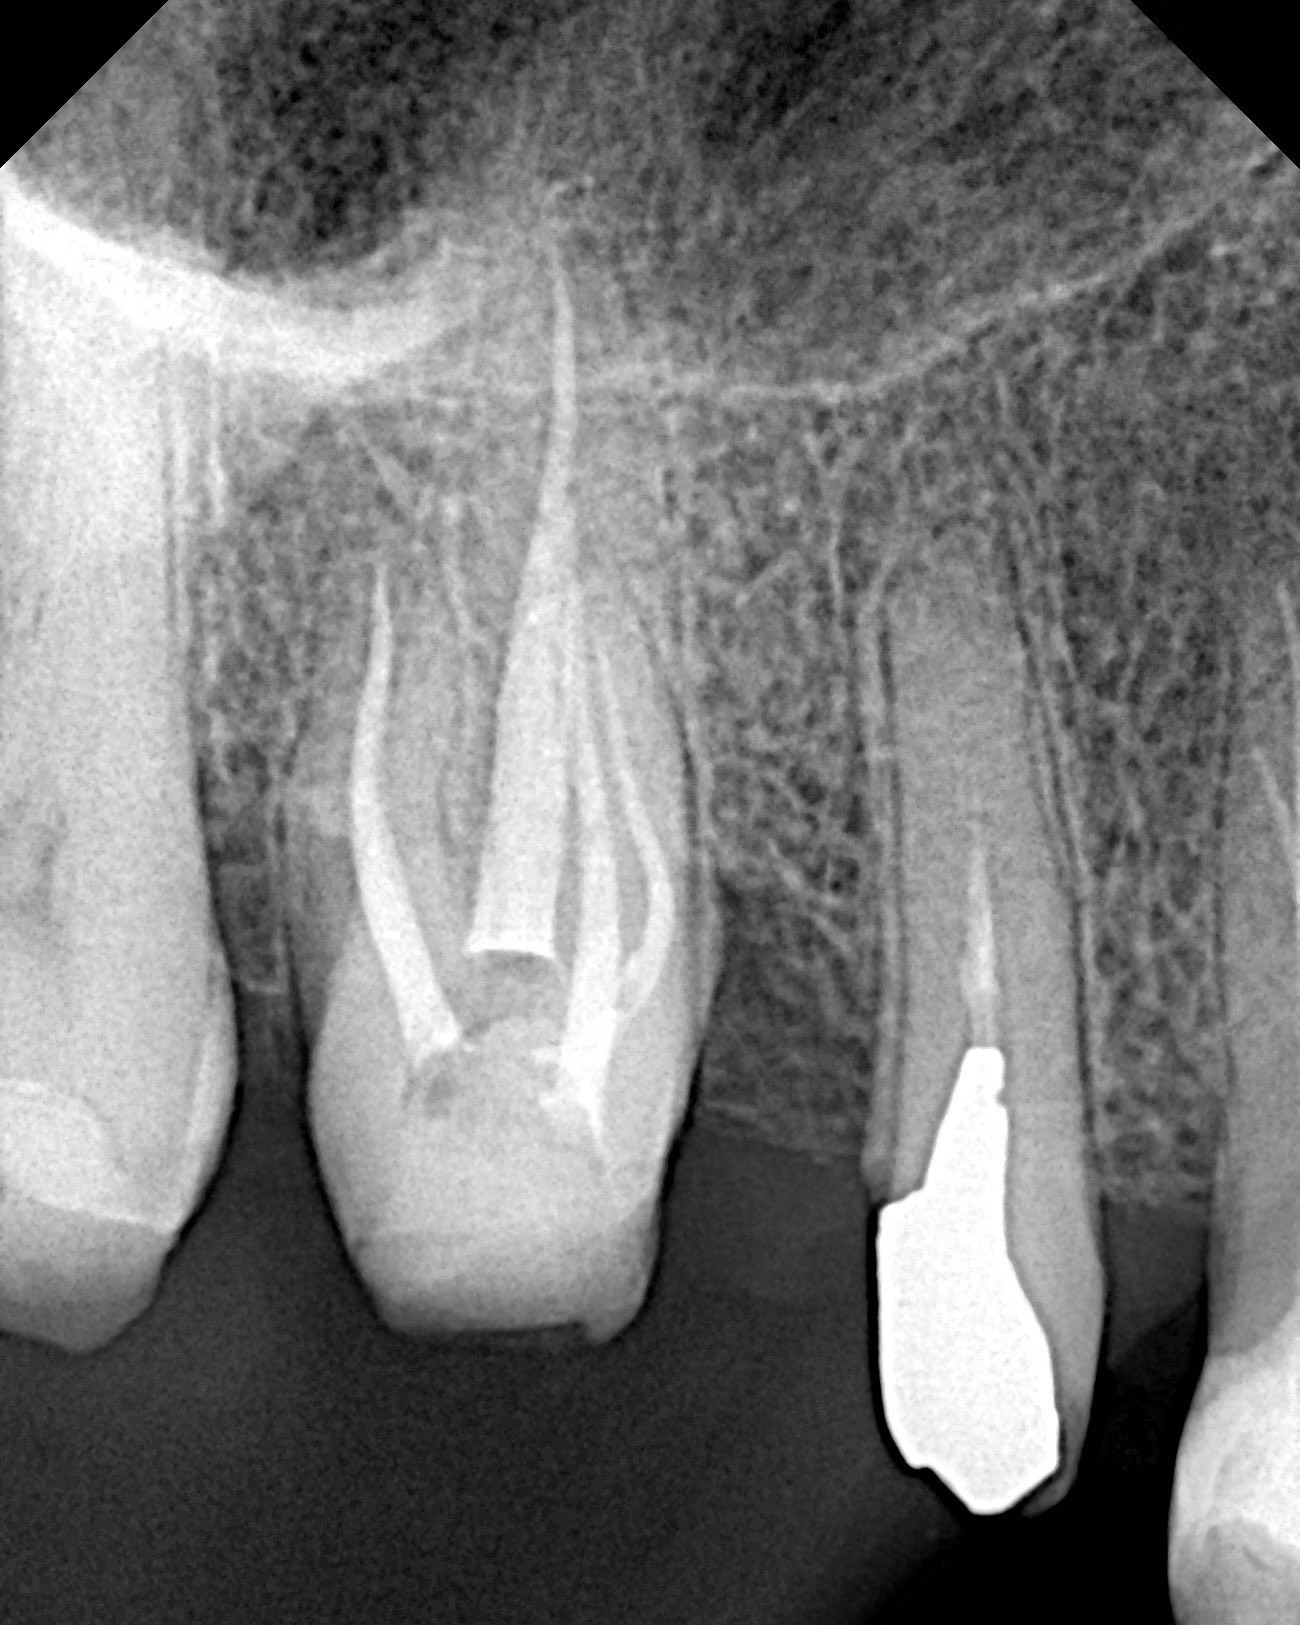

Cu toate astea există și situații când trebuie să refacem un tratament chiar dacă dintele nu prezintă simptomatologie. Intervenția are scop preventiv (dintele să nu devină simptomatic) și este dictată de examenul radiologic de cele mai multe ori (canale ratate, perforații, instrumente fracturate, etc). În acest caz dintele 1.6 avea o coroană veche ce trebuia schimbată. Am analizat radiografia și am observat ca tratamentul endodontic anterior nu putea susține un prognostic bun pe termen lung al dintelui.

Împreună cu pacientul am decis refacerea tratamentului. Astfel obturația endodintica veche a fost îndepărtată, canalele omise au fost reperate, instrumentate și dezinfectate iar la final au fost obturate prin tehnica condensării verticale la cald.